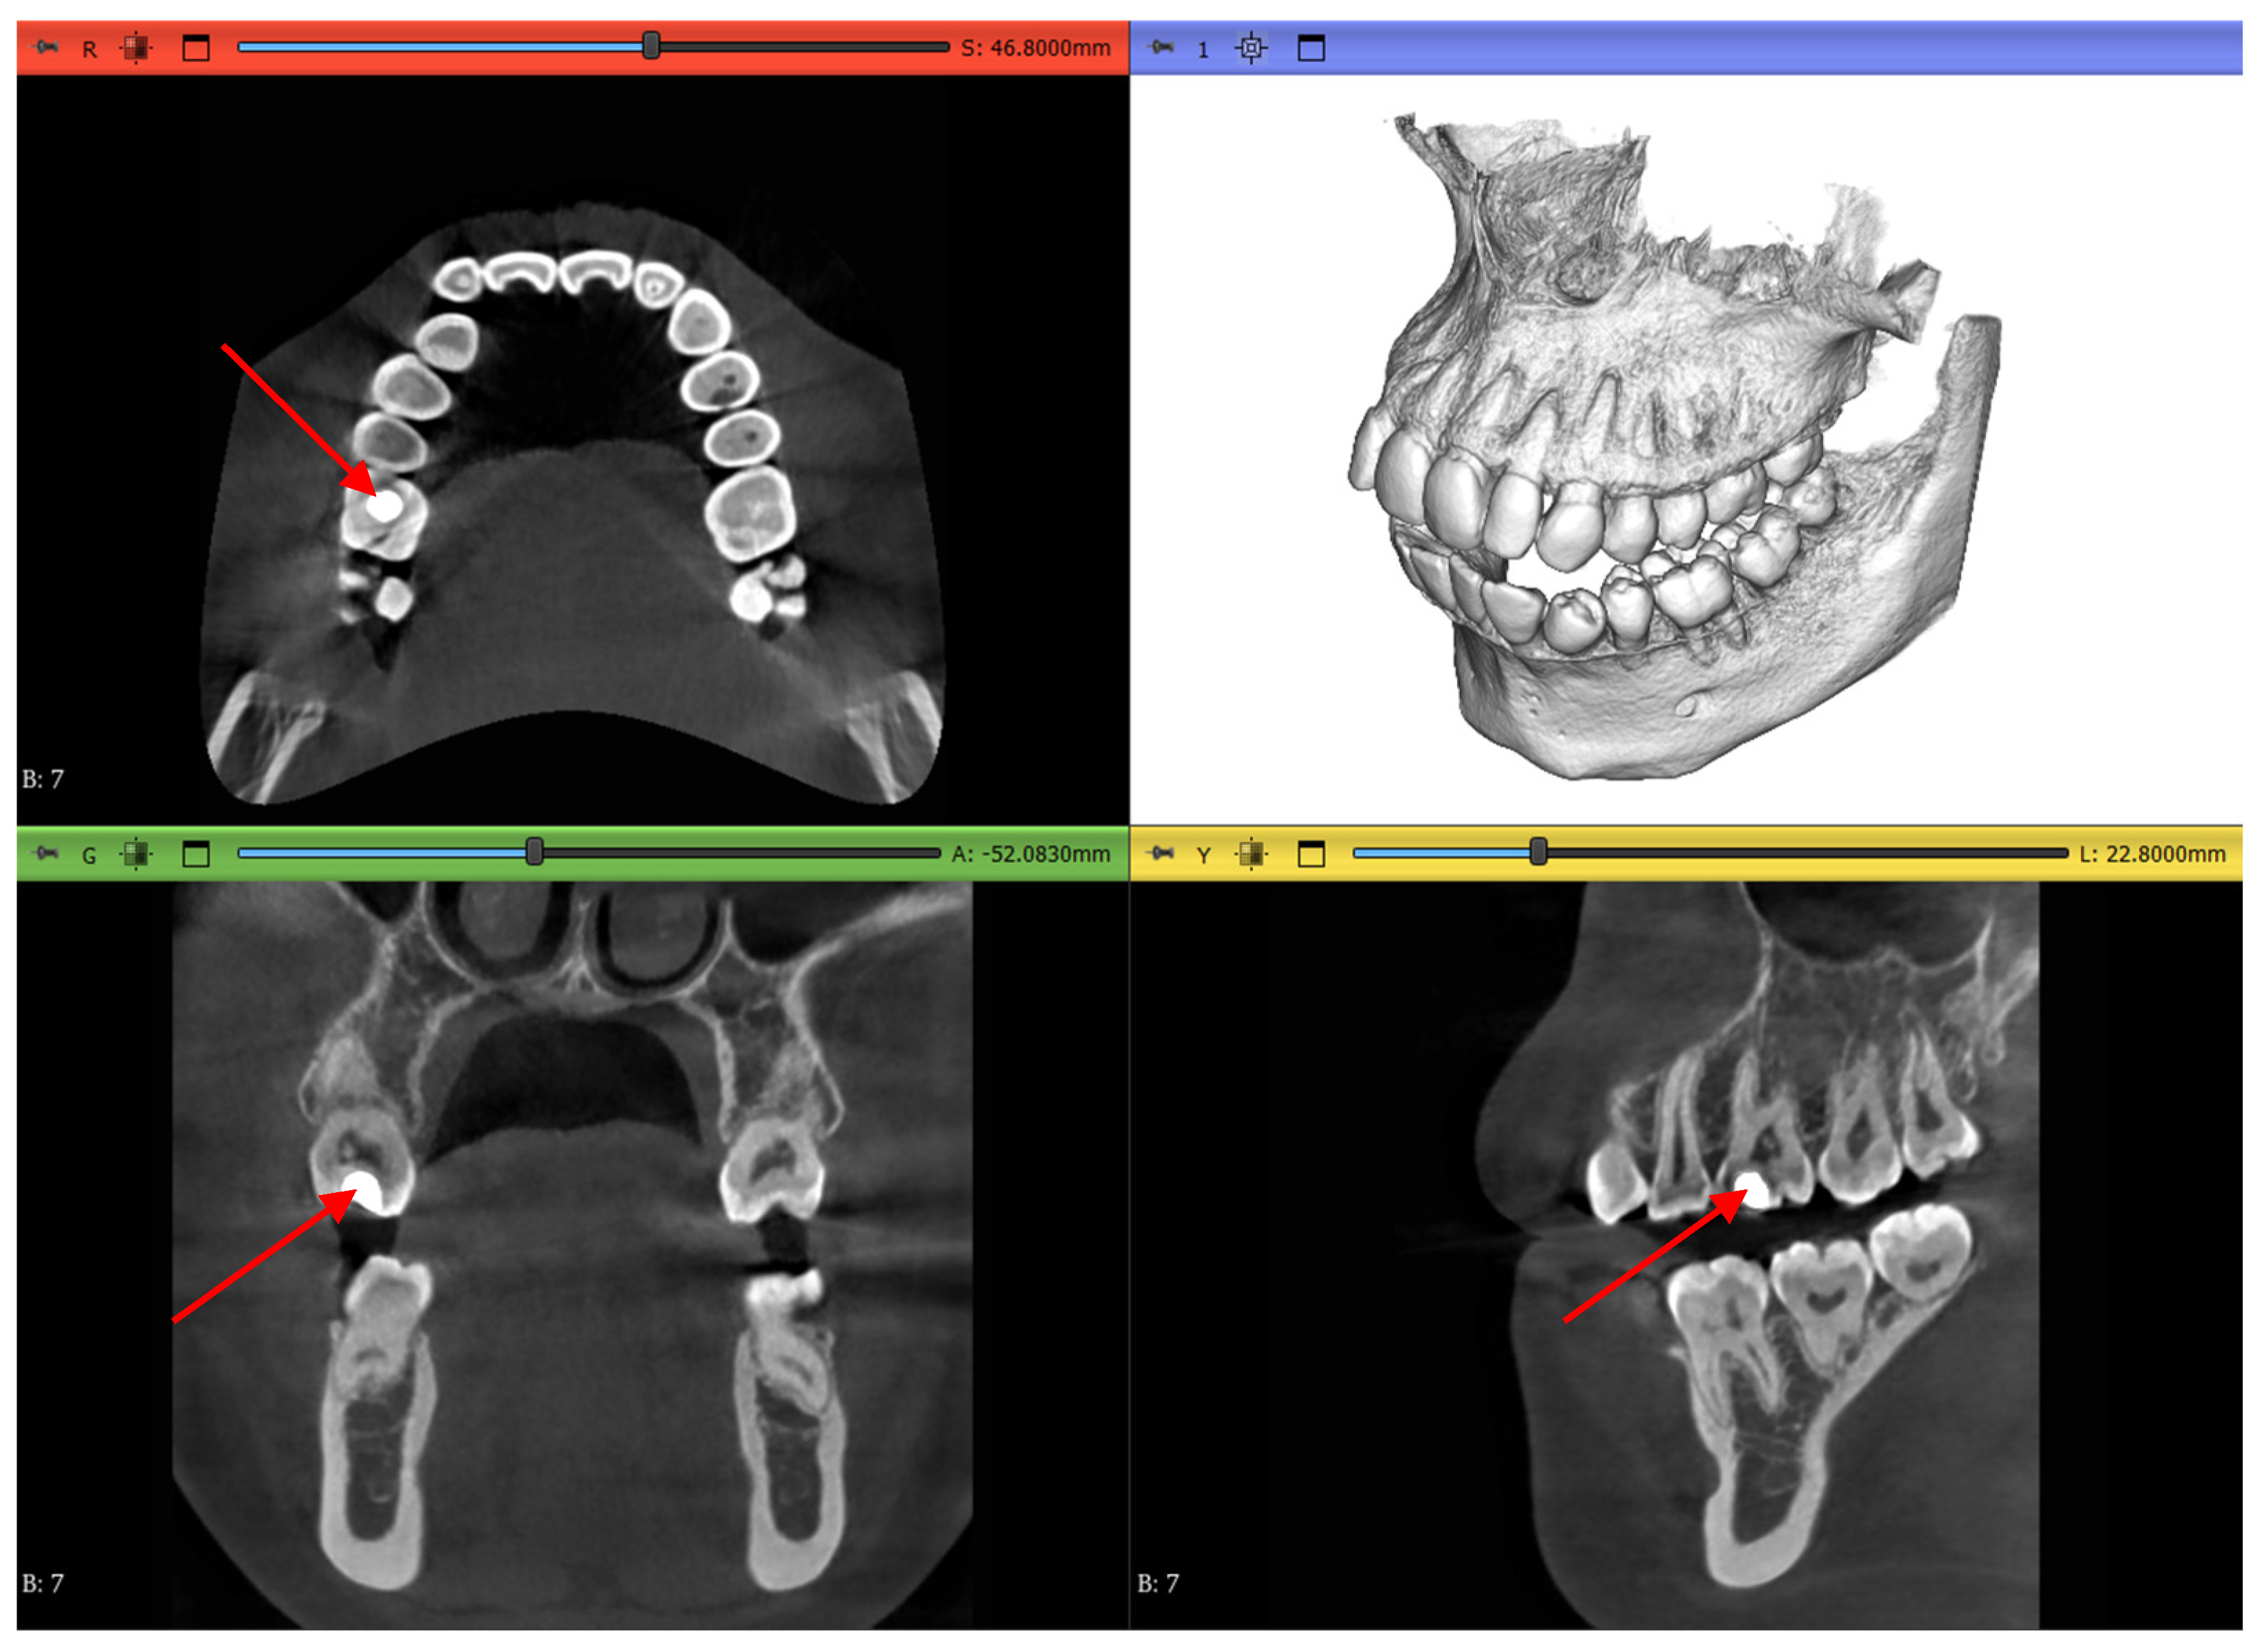

2.3.1. Volume Cropping

2.3.2. Histogram Adjustment